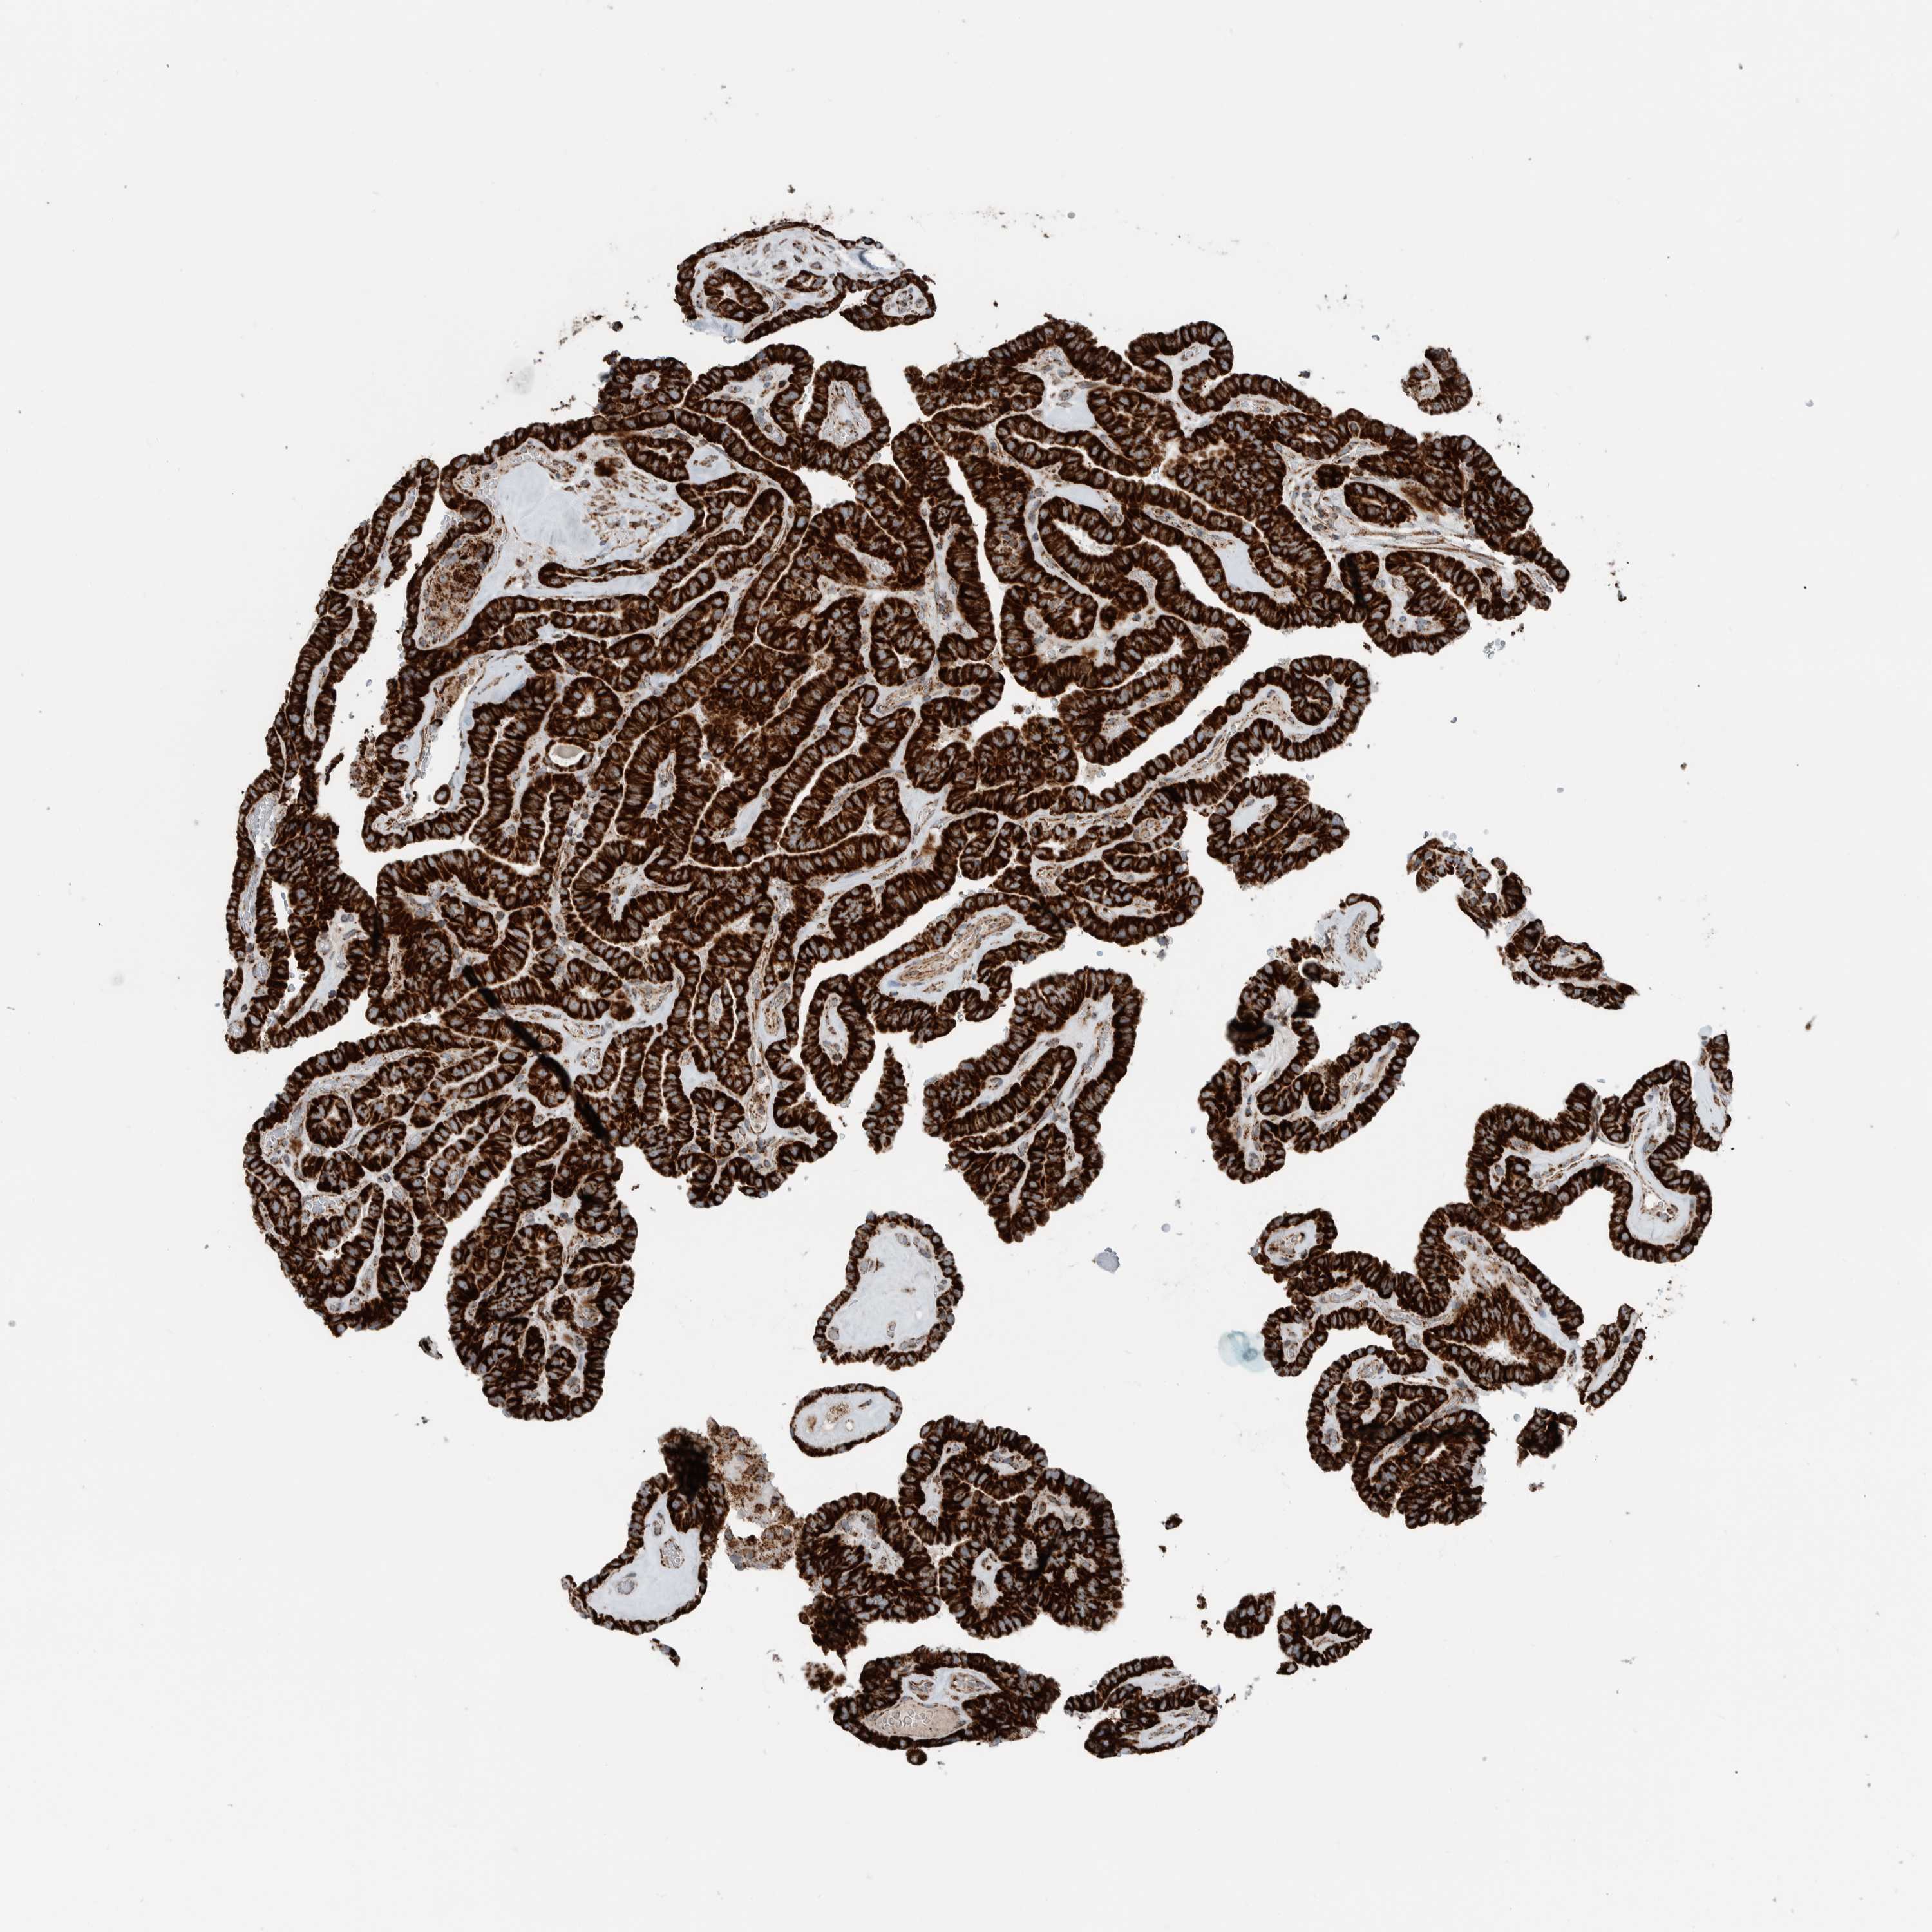

THYROID CANCER - Protein expressioni

A mouse-over function shows sample information and annotation data. Click on an image to view it in a full screen mode. Samples can be filtered based on level of antibody staining by selecting one or several of the following categories: high, medium, low and not detected. The assay and annotation is described here.

Note that samples used for immunohistochemistry by the Human Protein Atlas do not correspond to samples in the TCGA dataset.

Antibody stainingi

Antibody staining in the annotated cell types in the current human tissue is reported as not detected, low, medium, or high, based on conventional immunohistochemistry profiling in selected tissues. This score is based on the combination of the staining intensity and fraction of stained cells.

Each image is clickable and will lead to virtual microscopy that enables deeper exploration of all samples and also displays staining intensity scores, fraction scores and subcellular localization as well as patient and tissue information for each sample.

Antibody HPA023319

Antibody HPA023320

Antibody HPA023321

Antibody HPA023325

Staining

High

Medium

Low

Not detected

Intensity

Strong

Moderate

Weak

Negative

Quantity

>75%

75%-25%

<25%

None

Location

Nuclear

Cytoplasmic/membranous

Cytoplasmic/membranous,nuclear

Papillary adenocarcinoma, NOS

Follicular adenoma carcinoma, NOS